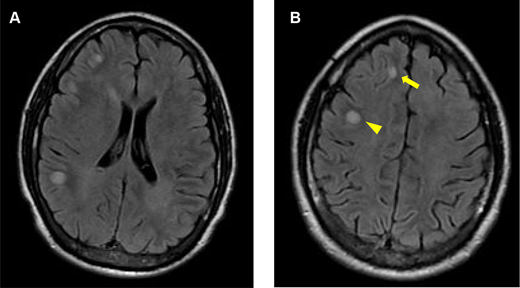

The patient’s magnetic resonance imaging (MRI) of the brain at presentation. A, axial fluid-attenuated inversion recovery (FLAIR) imaging of the brain shows multifocal hyperintensities at the gray–white matter interface. B, axial FLAIR imaging of the brain shows a hyperintense lesion at the right frontal gray–white matter interface (arrow) and a hyperintense lesion in the right frontal white matter (arrowhead).

A 29-year-old previously healthy man developed mild COVID-19 in October 2023, recovering within two weeks. In late December 2023, he experienced a generalized tonic-clonic seizure, followed by transient right arm rigidity and postictal aggression. Brain MRI revealed multifocal juxtacortical T2/FLAIR hyperintensities with faint gadolinium enhancement. CSF analysis showed no pleocytosis, a normal IgG index, and an absence of oligoclonal bands. MOG and AQP4 antibodies were negative, ruling out neuromyelitis optica and MOG-associated disorders. High-dose corticosteroids resolved the lesions, as observed on follow-up imaging in January 2024.